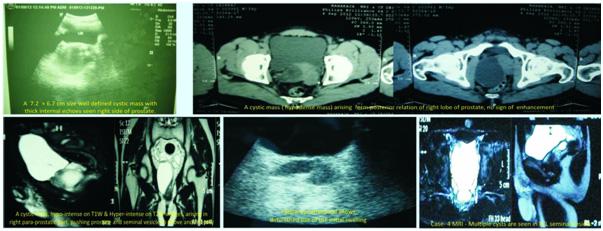

Ultrasound studies : Ultrasound showed cystic lesions in 17 patients and solid masses in three. Medial locations of a cystic retro-vesical mass were consistent with a prostatic utricle cyst (Fig 1) or abscess (Fig 2). Transrectal ultrasound was performed

additionally in eight patients to confirm the intraprostatic or extra-prostatic location of the cysts. Ultrasound revealed mixed echogenic masses in all the three patients with retro-vesical teratoma (Fig 3) which was difficult to differentiate from haematoma and four patients had cystic lesion contained hyperechoic material consistent with dermoid cyst but one letter on confirm on HPE was mullerian duct cyst with cystadenoma. A cystic extra-prostatic mass lateral to

the bladder neck was demonstrated on ultrasound for all seminal vesicle (Fig 4).

IVU, CYSTOGRAM, AGP and Vasography : One patient reported large mass shadow seen in pelvis left side pushing bladder towards right and anteriorly with raised base of the bladder. Vasography -B/l vas and seminal vesicle normal, bladder base elevated and grade 1 reflex on left side (Fig 5) (mullerian duct cyst with cystadenoma). In Case-4 vasogram confirm the

Fig 4 — USG images of seminal vesicle cyst Fig 1 — USG images showed prostatic cyst Fig 3 — Radiological images of Teratoma (case no 5)

Fig 2 — Radiological pictures of Epidermoid cyst (case no 3) and Last MRI picture showed b/l seminal vesicle cyst (case no 4)

CT scan and/or MRI abdomen pelvis : CT Scan and/ or MRI abdomen pelvis was performed in 16 cases, both were accurately demonstrated the anatomical relationship of associated intra pelvic organs with surrounding fat and pelvic lymph nodes. CT Scan and/ or MRI abdomen pelvis clearly depicted prostatic utricle cysts in 3/3(100%) cases, intraprostatic abscess cavities in 2/2 (100%) cases, seminal vesicle cysts 2/ 2 (100%) and cystic connective tissue masses in 4/4 (100%). CT scan abdomen pelvis accurately demonstrated retro-vesical connective tissue solid masses in three cases. CT scan and/or MRI abdomen pelvis failed to differentiate accurate diagnosis in two cases (ejaculatory duct cyst and mullerian duct cyst with cystadenoma). However, MRI failed to differentiate between teratoma and haematoma. FNAC accurately demonstrates diagnosis in two cases of intraprostatic abscess (Fig 6).